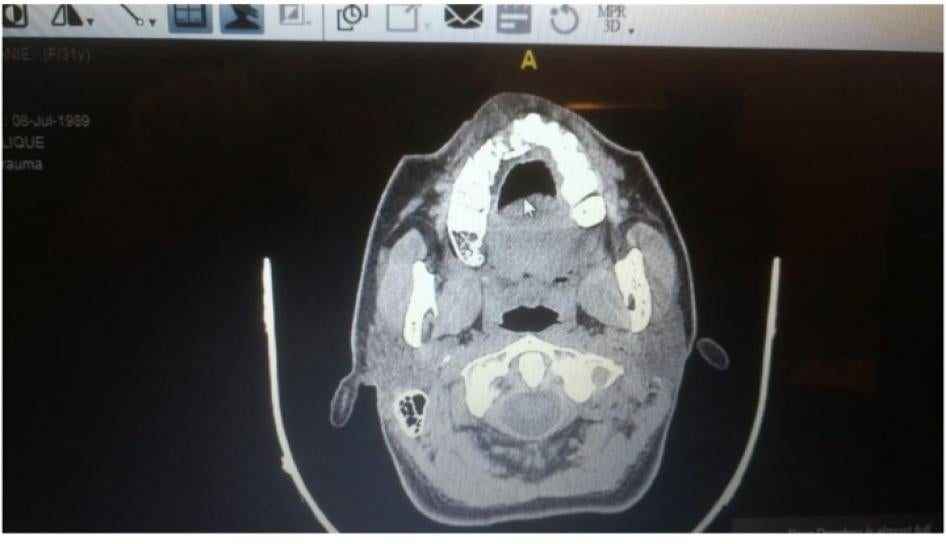

راجعت هيومن رايتس ووتش السجلّات الطبية لعمر في 8 أغسطس/آب، بما فيها صور الأشعّة السينية التي أظهرت ثلاث شظايا كبيرة من الرصاص وشظايا عديدة أصغر في رجله اليسرى. قال: "لحسن الحظ، لم تصل الرصاصة إلى عظمي. كانت قريبة من الشريان، لكنّها بالكاد لم تلامسه".

أطلقت القوات الأمنية رصاصة على عمر فأصابت أعلى فخذه الأيسر. الصورة على اليسار تظهر جرح دخول الرصاصة. تُظهر الأشعة السينية ثلاث شظايا رصاصة كبيرة وعدة شظايا أصغر في ساقه اليسرى، والصورة على اليمين تُظهر الشظايا المستخرجة من ساقه.  © 2020 تقدمة عمر